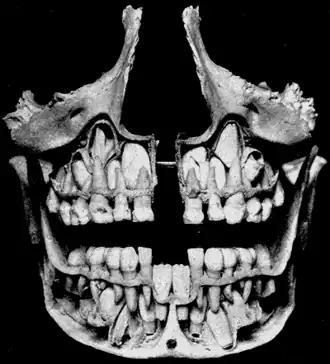

Cross-section of upper and lower jaws with permanent teeth located above and below the deciduous teeth prior to their exfoliation. The deciduous mandibular central incisors have already been exfoliated.